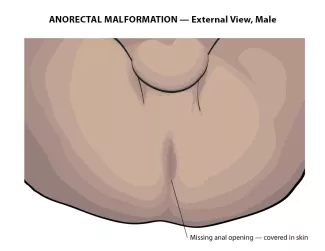

The diagnosis is made by physical examination. If the anal opening is absent or in the wrong spot, it can be seen on examination. If there is stool coming out of the urethra, or vagina, instead of the anus, it will be visible. In females with anorectal malformation, careful examination of the vestibule (area between the labia) must be made to ensure separate openings of the urethra and vagina. In the males with imperforate anus, careful examination of the perineum is necessary to identify any abnormal passage of stool.